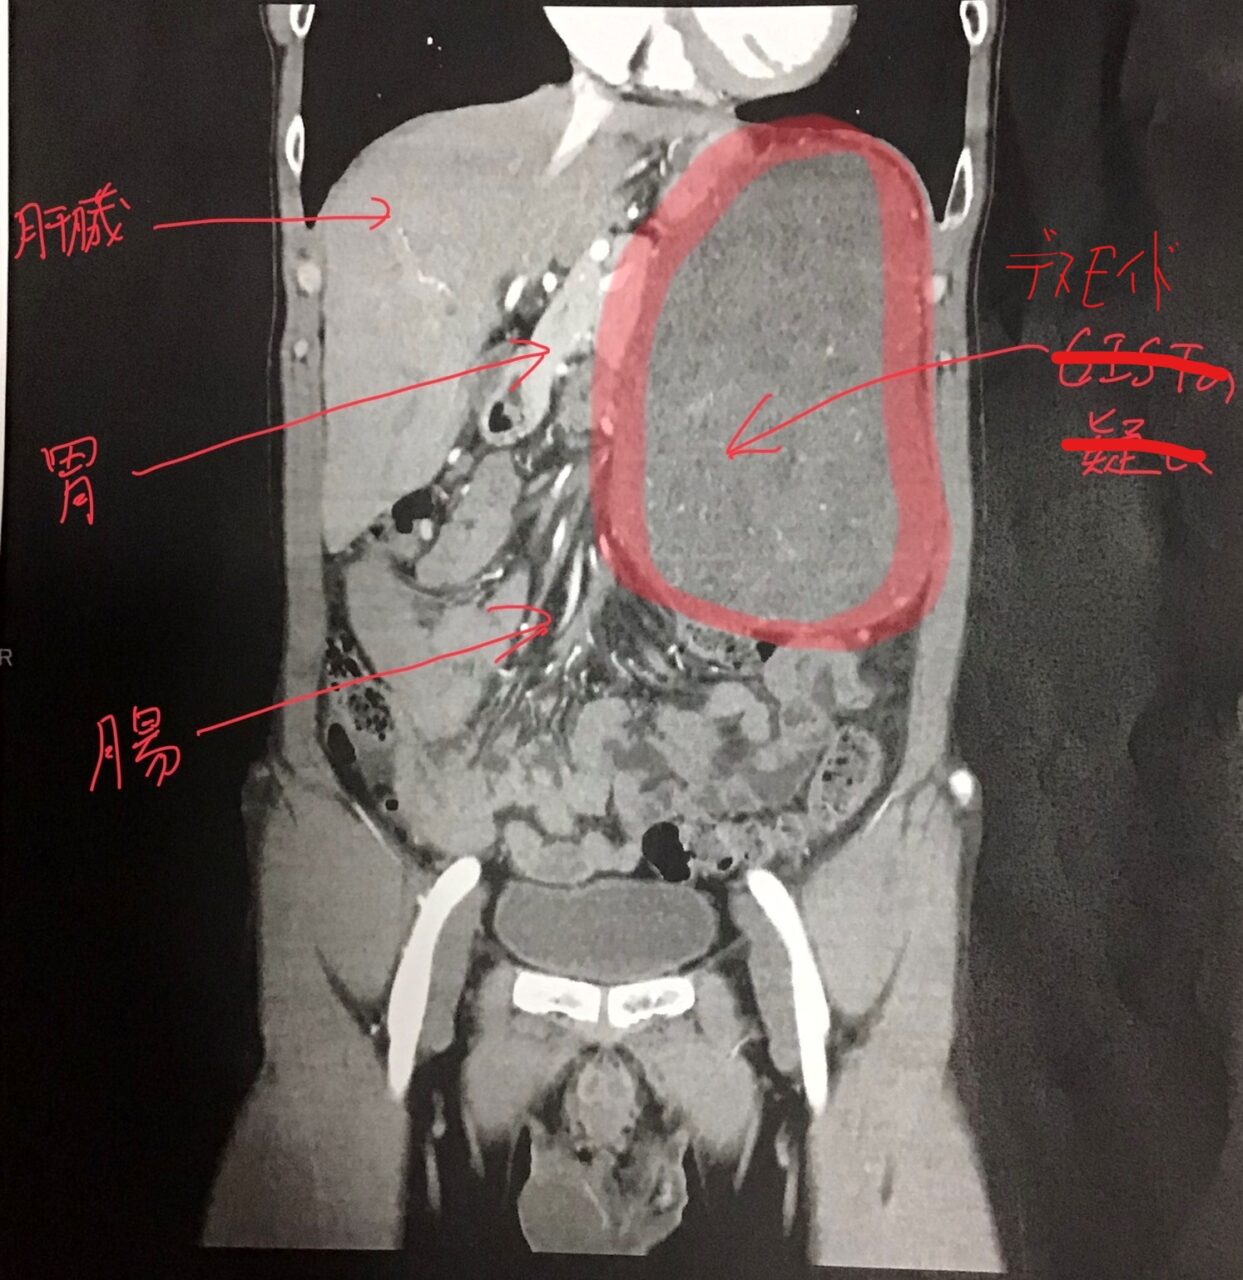

手術から7.0年が経過した。半年ごとの定期検査ですが、今回は腹腔内デスモイドの件があるので心配。

腹腔内デスモイドの話と、家族性大腸ポリポージスの疑いがあることを先生に伝えると、脳腫瘍と関係しているかもしれないね、とのこと。